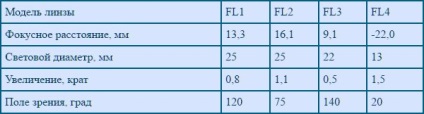

În România, obiectivul fundus produce „OLIS firmă“, unii dintre parametrii tehnici ai care sunt prezentate în tabel.

Fig. 3 (Specificații tehnice).

Modele FL1 lentile Fundus - FL3 format opus unei imagini reale (pentru FL1 și FL3 - redusă și pentru FL2 - agabaritice). lentilă FL4 oferă o imagine mare imaginar directă.

Partea optică a modelelor FL1 si FL2 este format din două lentile, FL3 are, de asemenea, un obiectiv intermediar; Modelul FL4 - o singură lentilă negativă. Lentilele sunt realizate din silicat de sticlă optică. La observarea lentilei este acoperită de acoperire antirefleksnoe pentru regiunea spectrală vizibilă. Lentilele sunt sigilate, au flanșe haptice pentru o mai bună fixare în cercetare.